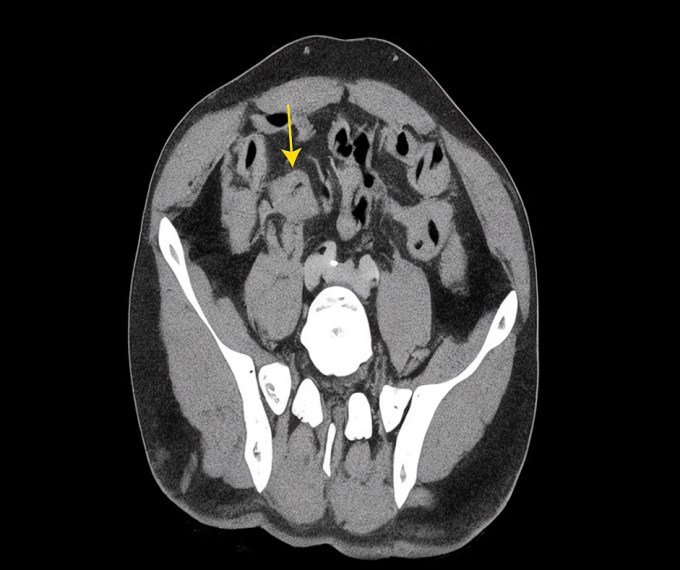

Giải phẫu bệnh xác định ung thư biểu mô tuyến xâm nhập, biệt hóa vừa. Tiến sĩ, bác sĩ Phạm Công Khánh, Trưởng khoa Gan - Mật - Tụy, Trung tâm Nội soi và Phẫu thuật Nội soi Tiêu hóa, chẩn đoán ông anh Ngọc ung thư manh tràng - đại tràng lên giai đoạn muộn, di căn gan tại hạ phân thùy ba.

Theo bác sĩ Khánh, thông thường ung thư đại trực tràng đã di căn gan ít có khả năng phẫu thuật. Tuy nhiên, trường hợp này khối u gan di căn khu trú ở thùy trái gan nên vẫn có thể cắt bỏ hoàn toàn. "Nếu phẫu thuật, tỷ lệ sống sau 5 năm của bệnh nhân có thể 40-60%", bác sĩ Khánh nói.

Sau hội chẩn, các bác sĩ quyết định phẫu thuật đồng thời cắt đại tràng phải, nạo vét hạch và cắt khối u gan di căn trong cùng một cuộc mổ. Mổ "2 trong 1" giúp bệnh nhân chỉ trải qua một lần gây mê, rút ngắn thời gian hồi phục, sớm hóa trị bổ trợ, đồng thời giảm số lần nằm viện.